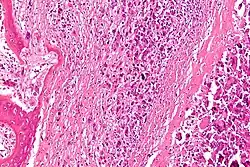

![]() Obraz histologiczny kostniakomięsaka |

Kostniakomięsak, mięsak kościopochodny (łac. osteosarcoma) – grupa pierwotnych nowotworów złośliwych wywodzących się z prymitywnych komórek mezenchymatycznych klasyfikowanych do grupy pierwotnych wrzecionowatokomórkowych mięsaków tkanki kostnej produkujących osteoid[1][2].

Kostniakomięsak jest nowotworem złośliwym charakteryzującym się bezpośrednim i pierwotnym wytwarzaniem przez komórki nowotworowego osteoidu lub niedojrzałej tkanki kostnej[4]. Nowotwory złośliwe kości w klasyfikacji WHO są dzielone następująco[29][30]:

Mikroskopowo guz jest zbudowany z wrzecionowatych komórek, choć faktycznie cechuje go tendencja do znacznego pleomorfizmu i anaplazji, przez co komórki mogą przybierać różne formy. W większości przypadków stwierdza się dwa i więcej typów komórek tworzących nowotwór. Również jądro komórkowe cechuje znaczny pleomorfizm. Nowotwór z definicji wytwarza osteoid, ale również może wytwarzać tkankę chrzęstną lub włóknistą. Ze względu na dominującą substancję pozakomórkową klasyczny kostniakomięsak może być dalej dzielony na postać osteoblastyczną, chondroblastyczną i fibroblastyczną[20][46].